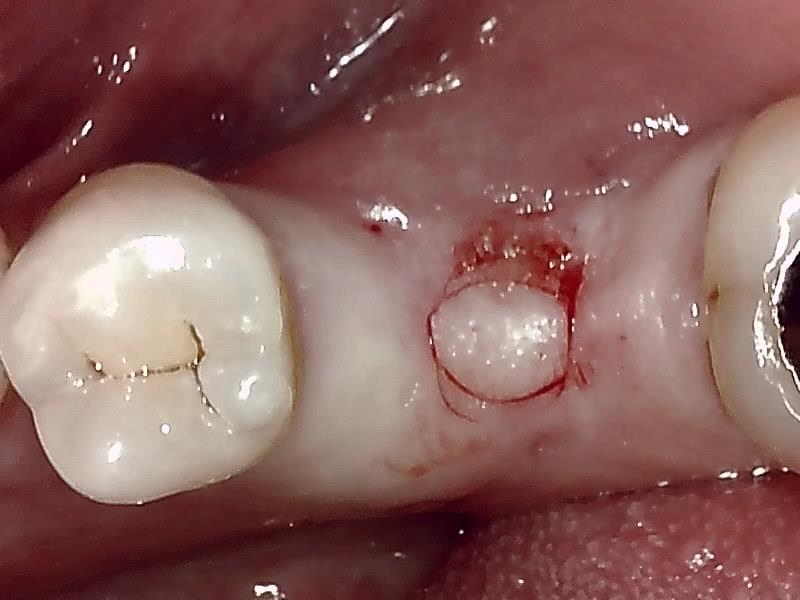

顎堤歯肉をくり抜き切開して歯肉片を温存する。

顎堤部 歯槽骨にドリリングする。

インプラント体の口径に合わせて埋入孔を形成した状態です。